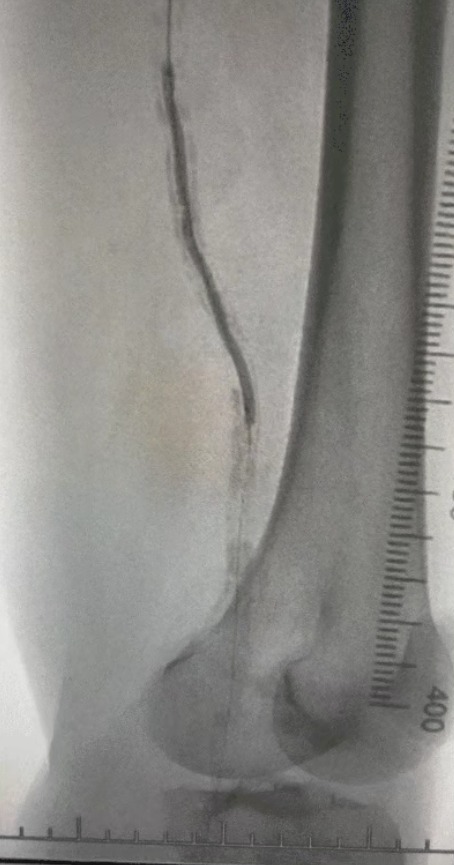

・術前イメージング: 両側下肢動脈における重度のびまん性石灰化狭窄症

複雑な血管状態を考慮して、ThorCrack末梢IVLバルーン拡張カテーテルシステムを選択しました。 患者の耐性が限られているため、両方の下肢に段階的な介入手順が実行されました。

外科的成果

処置後、動脈狭窄は大幅に改善し、血流が増加し、皮膚の温度が上昇しました。 術後の合併症は発生しませんでした。 患者と外科チームの両方が結果に非常に満足していました。